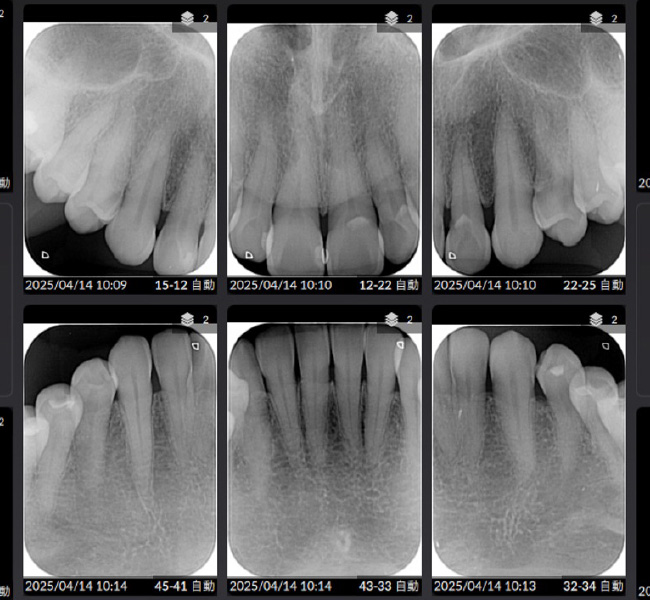

治療後

| 主訴 | 左奥歯が仕事が忙しくなると上下とも痛くなる。 毎月メインテナンスしていた歯科医院が閉院した。 歯周病含め今の状態が気になる。 全体のメインテナンスもしたい。矯正治療はやりたくない。 |

| 治療内容 | 全顎治療:歯周病治療、根管治療、 歯肉弁剥離掻爬術(フラップ手術)、 セラミック治療、ダイレクトボンディング |